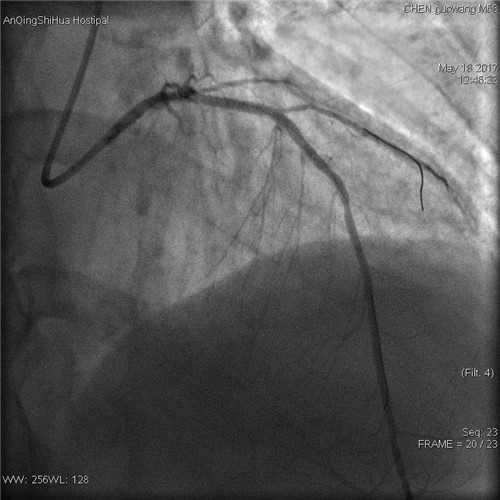

術(shù)后 前降支支架內(nèi)狹窄解除